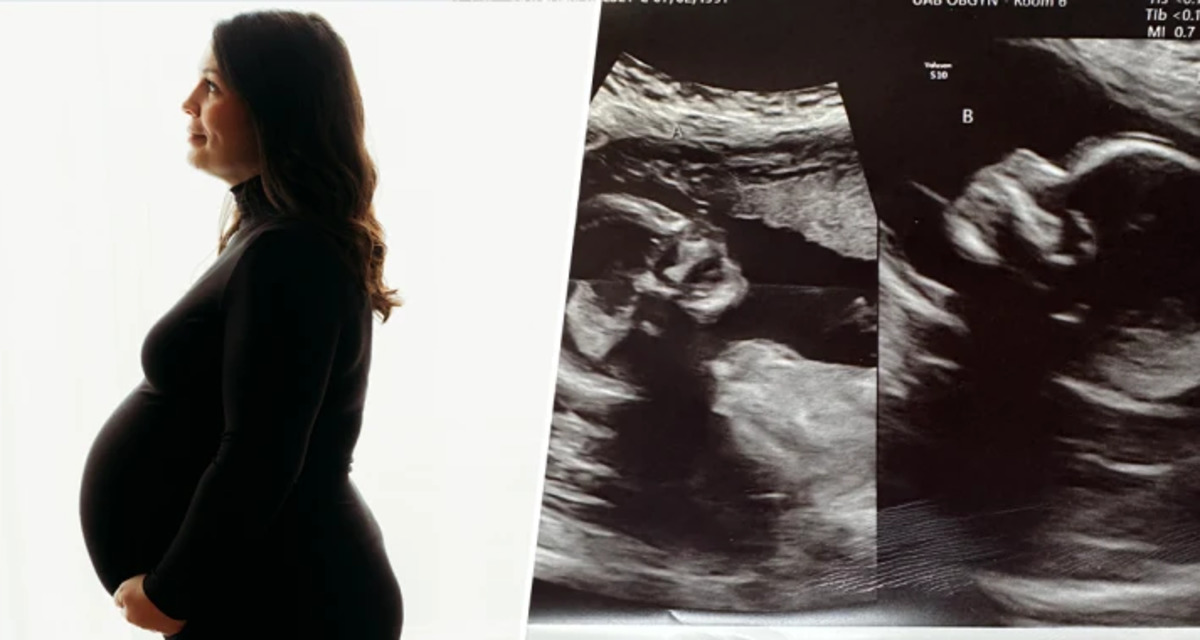

केल्सी ने बताया कि मई में जब वह 8 हफ्ते की प्रेग्नेंट थी, तब एक अल्ट्रासॉउन्ड के दौरान उसे यह पता चला कि वह 2 बच्चों की माँ बनने वाली है और दोनों यूटेरस से बच्चों को जन्म देगी।

अल्ट्रासॉउन्ड से पता चला कि 2 बच्चों की बनेगी माँ